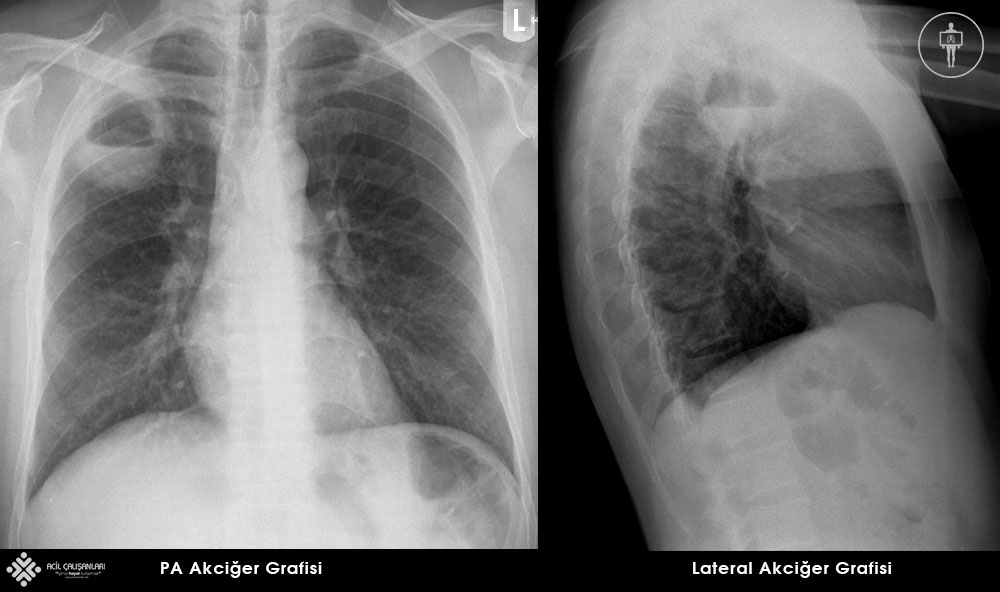

Akciğer

Akciğer parankim alanları sağdan sola, yukarıdan aşağıya ya da kişinin kendi seçeceği bir yolla herhangi bir alan atlamadan tamamen gözle taranmalıdır. PA grafiye göre lob ve segmenlerin yeri tam olarak belirlenemez bu yüzden zon tabiri kullanılır. Akciğer 2. ve 4.kotlardan geçirilen yatay çizgi ile üst-orta ve alt zonlara ayrılarak incelenir. PA grafinin en büyük kısmını oluşturan parankim alanlarındaki her tür opasite veya radyolusan alan tanısal değer taşıyabileceğinden atlanmaması önemlidir. Parankim değerlendirmesi sırasında özellikle travma ve yoğun bakım hastalarının pnömotoraks gelişimi ve kateterler açısından da incelenmesi önem taşır. Filmde plevral efüzyon mutlaka aranmalı, kostofrenik açının açıklığı not edilmelidir. Plevral kalınlaşmalar ve özellikle kalsifikasyonlar grafide parankim ile süperpoze olup karmaşık görüntülere neden olabilirler.

Pozisyon: Posteroranterior akciğer grafisinde hasta göğüs ön duvarını filmi taşıyan kasede yaslar ve X-ışını yaklaşık 180 cm arkada bulunan kaynaktan göğüs posterior duvarına yönlendirilerek görüntü elde edilir. Aradaki mesafenin nedeni ışının yayılmasından kaynaklanan ve tüpe yakın yapıların büyük görünmesine neden olan etkiyi kaldırmaktır. Anteroposterior (AP) grafilerde büyütme etkisi belirginleşir ve kasetten uzak X-ışını kaynağına yakın yer alan kalp ve vasküler yapılar büyük görünürler.

Posteroranterior akciğer grafide filmin üst sınırı C7 vertebra düzeyini içerisine almalıdır. Larinks ve kostofrenik açılar grafi alanında olmalıdır. Işın T4 vertebra düzeyine santralize edilir. Her iki skapula akciğer alanları dışında tutulacak şekilde hastaya pozisyon verilir.